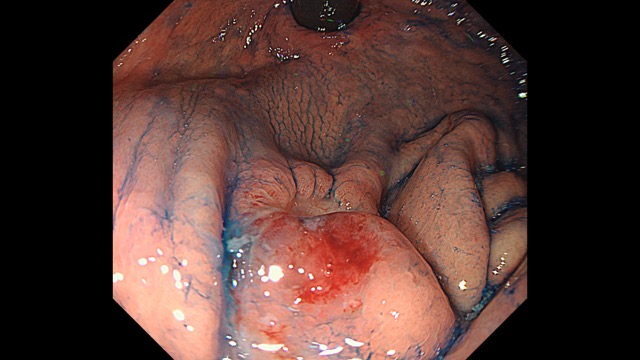

Gastrointestinal Mapping ~Stomach~ 2025.8.27